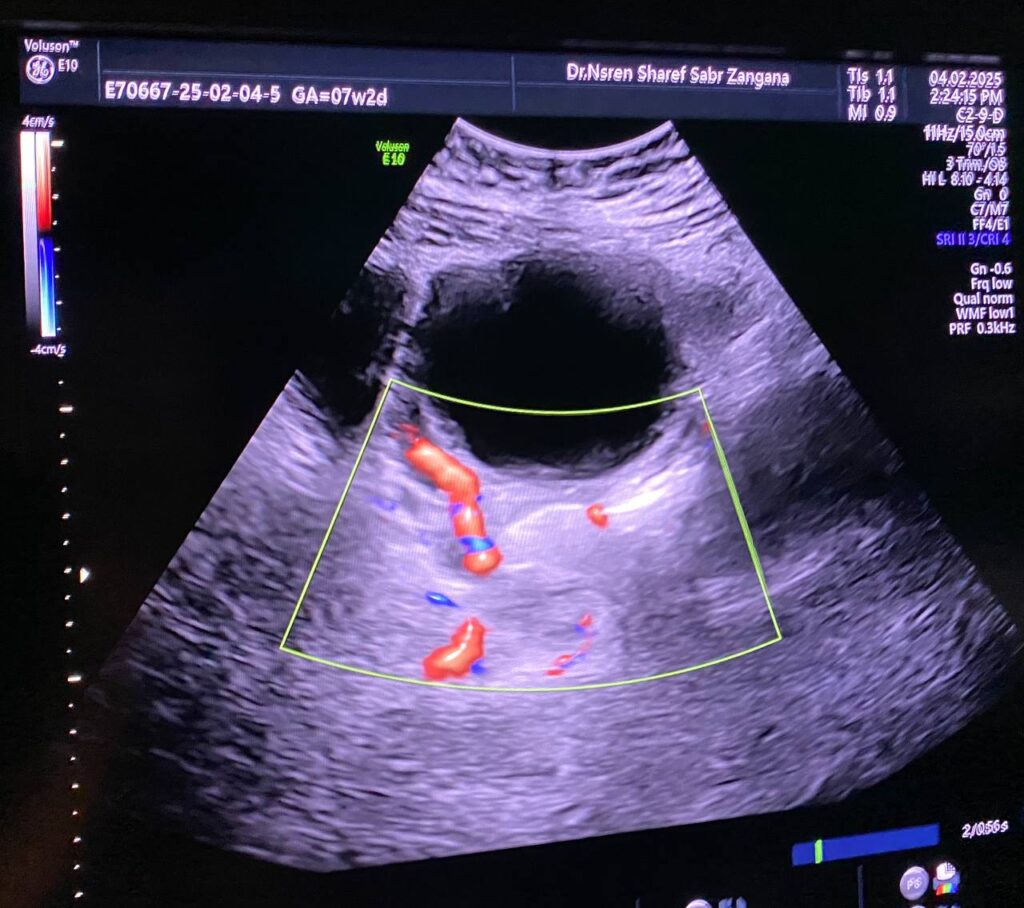

Left ovarian avascular cystic mass 71x68mm , with adjacent left adnexal mass 30x30mm , picture mostly of twisted ovarian pedicle , associated with free fluid >40ml , please for further study to excluded other pathology

Lt ovary is enlarged and edematous, contains 7cm thin wall unilocular cyst “ORADS 1”, there is twisting of its vascular pedicle, picture of ovarian torsion.